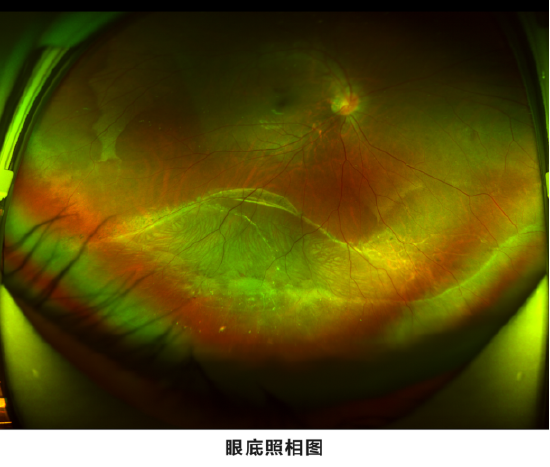

关注今年夏天,踌躇满志计划应征入伍的男孩小汤到龙岩爱尔眼科做近视手术术前检查,准备把“陪伴”他十多年的高度近视眼给矫正了。然而,不检查不知道,一检查吓一跳,术前眼底检查发现小汤的右眼视网膜下方有视网膜网格样变性合并视网膜脱离。

“平时我的眼睛并没感觉任何异样啊!”看到眼底检查结果的小汤大受震撼。屈光手术专科高俐主任告诉他,因为目前病变部位还未扩展到黄斑区及视乳头区范围,所以小汤视物目前尚未受到影响。但千万不能抱有侥幸心理放任不管,因为这种病变是会发展的,若未及时进行治疗,随着发展范围的扩大,迟早会影响黄斑区及视乳头从而影响视力。到时再进行治疗也迟了,术后视力和恢复情况都会受到影响,造成不可逆的视觉损伤。

据高俐主任科普,对于视网膜周边裂孔及有较大危险性发生裂孔的视网膜变性区,一般要先进行视网膜激光光凝包绕,以减少术后发生视网膜脱离的可能性。对眼底进行激光治疗一周后,如果复查视网膜的恢复情况良好,经再次散瞳确认视网膜治疗区无异常后,即可考虑做屈光手术。